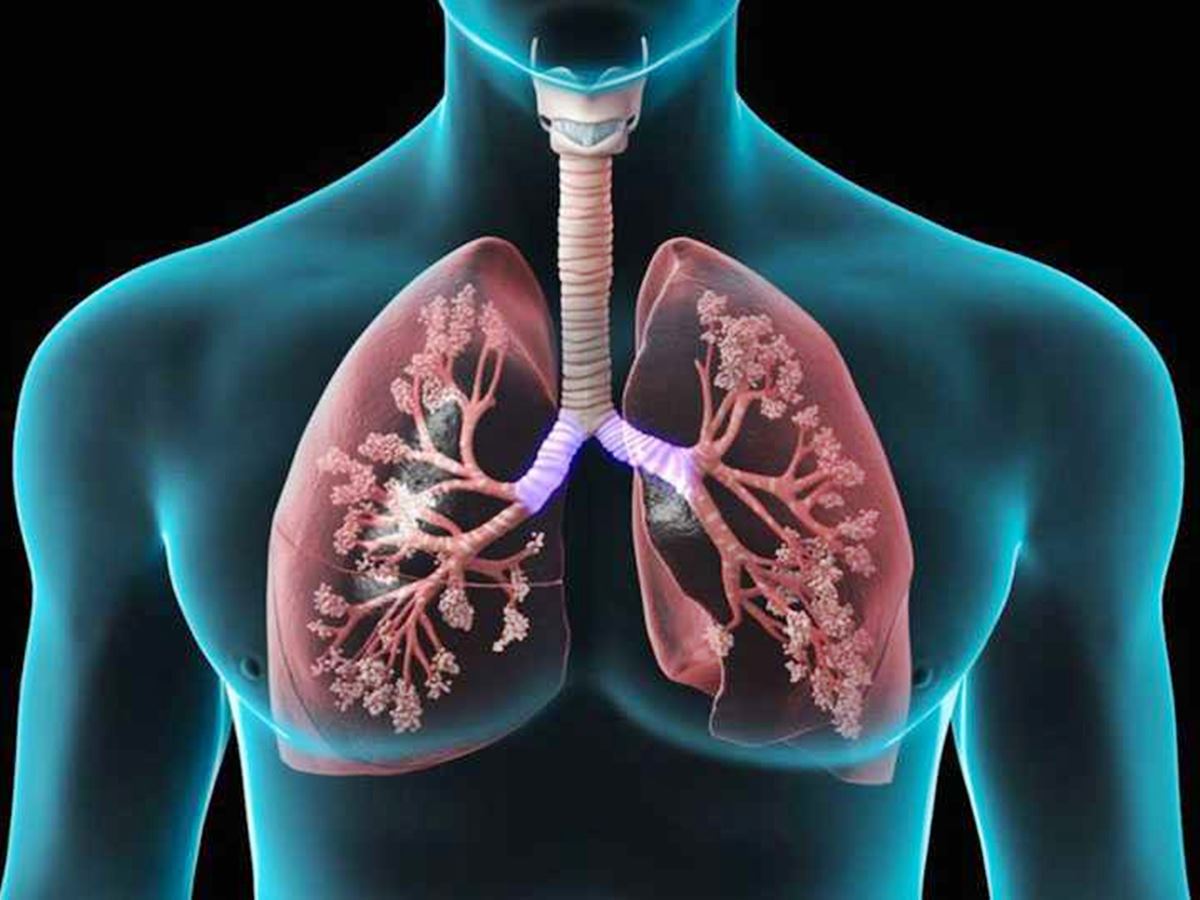

O inverno chega oficialmente no próximo dia 21 de junho e, com ele, o aumento de gripes e doenças respiratórias, incluindo a temida covid-19. Médicos alertam para a importância de reforçar a imunidade e cuidar da saúde durante o período. “Com algumas medidas e tratamentos adequados é possível atravessar essa fase sem complicações mais sérias”, orienta a médica ortomolecular e geriatra, Márcia Umbelino.

De acordo com a médica, além da gripe, as doenças mais comuns no inverno são o resfriado, a exacerbação da asma e doenças pulmonares obstrutivas crônicas, como o enfisema e a bronquite do fumante. São doenças que fazem parte do sistema respiratório, que são desencadeadas por gatilhos como mudança de temperatura, inalação de fumaça, poluição no ar, estresse e exercício físico. A doença atinge de forma mais intensa crianças e idosos, por isso, a vacinação contra gripe e pneumonia é fundamental nesse período.

Segundo dados da Organização Mundial de Saúde, cerca de 3,5 milhões de pessoas têm a saúde comprometida de alguma forma, anualmente, por conta do vírus da gripe, outros 300 milhões sofrem de asma e 250 milhões de rinite alérgica, números que podem chegar a 400 milhões até 2025. Segundo Márcia Umbelino, pessoas que sofrem de sinusite e asma podem ter o quadro agravado no inverno, o que facilita infecções como sinusite e pneumonia. A médica ressalta a importância das vacinas e também para tratamentos com vitaminas, aminoácidos e minerais para dar um reforço na imunidade.

Precursora de um inovador tratamento de soroterapia, Márcia costuma fazer combinações de suplementos com medicação para diminuir o processo inflamatório e parar os receptores histamínicos. “A vantagem da soroterapia é que ela substitui até 20 cápsulas diárias por uma única dose semanal de soro. A soroterapia ainda desinflama os tecidos e têm menor perda de substâncias por ser intravenosa”, explica a médica.

As doenças respiratórias são mais perigosas para os idosos e demandam certos cuidados, pois as pessoas de terceira-idade podem apresentar sintomas diferentes das demais faixas etárias. No caso de um resfriado, os sintomas costumam ser brandos, com coriza, leve dor de garganta e um pouco de dor de cabeça. Já a gripe deixa o paciente mais prostrado, cansado e, muitas vezes, com quadro febril e uma tosse mais forte que pode evoluir para um quadro infeccioso. A diferença no idoso é que ele pode não apresentar tosse, nem fadiga ou febre, mas sim desorientação. O geriatra, então, tem que estar ciente de que pode ser um quadro infeccioso ou viral, acompanhado de desidratação.

“Na asma brônquica o paciente já é inflamado. Então qualquer estímulo alergênico inflama mais, produz mais muco e o brônquio vai estreitar, o que vai dificultar a passagem de ar. Por isso que muitas vezes o paciente faz aqueles barulhos. É uma doença inflamatória e por isso se faz o tratamento convencional e a soroterapia também, porque ajuda a desinflamar”, finaliza Umbelino.